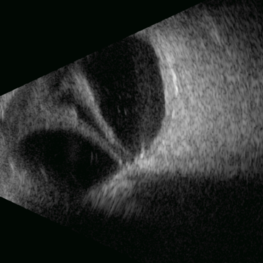

This B-mode transverse ultrasound scan reveals a chronic rhegmatogenous retinal detachment, demonstrating a funnel-shaped configuration with a narrow intraluminal space. Two hyperechoic choroidal calcifications are present, indicative of chronicity.

Photographer: Gustavo U. Fonseca Aguirre, Hospital Conde de Valenciana, Ciudad de México

Condition/keywords: open funnel RD, Retina detachment